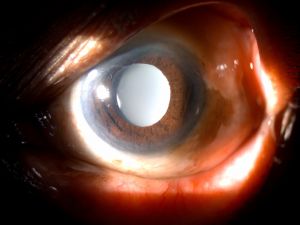

Clinical Diagnosis

The key to diagnosis is careful slit lamp examination in high magnification paying special attention to the IOL optic surfaces for signs of granularity or opacification. Slit lamp photography helps to monitor progression. Visual acuity and contrast sensitivity are reduced in IOL opacification cases.